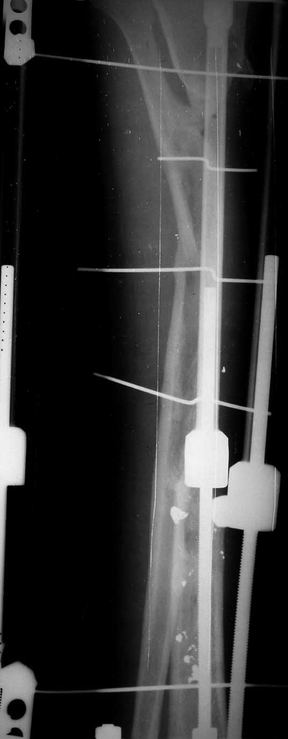

Отправлено Ласунский Сергей 30 Октябрь 2007, 23:53 РОСНИИТО им.Р.Р.Вредена

Пациентка с дефектом большеберцовой кости, возможно ли восстановление опороспособности нижней конечности? ДТП 1.5 года назад: открытый оскольчатый перелом средней трети левой голени с дефектом мягких тканей. Выполнены следующие операции в одной мз больниц города: 1.При поступлении ПХО и наложение АВФ 2.Нагноение резекция нежизнеспособной кости. 3.Пластика дефекта мягких тканей. 4.Попытка устранения дефекта по методу Илизарова, нагноение, радикальная хирургическая обработка, увеличение дефекта. 6 месяцев без признаков гнойного воспаления. В настоящее время иммбилизация гипсовой лонгетой до коленного сустава, функция коленного сустава сохранена, голеностопного нет.